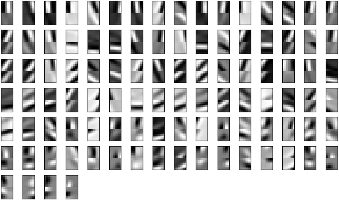

The training set is obtained from another breast sample imaged by the same technique but with an high quality reconstruction. We consider a slice image, we apply a Sobel filter to extract the two derivative components and we run the KSVD algorithm.

Figure 9 shows the patches basis functions that we use to fit both components at the same time. The patches size is pixels and each basis function is displayed as a rectangle whose upper part is the component and the lower one the component.